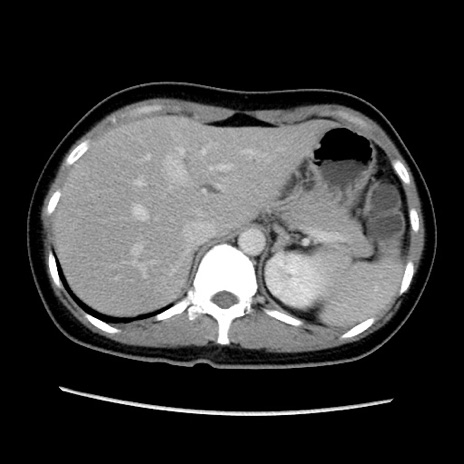

症例39(横断像)

【症例】40歳代女性

【主訴】上下腹部痛

【現病歴】2日目から下腹部痛あり。夜間は痛みで眠れなかった。昨日より上腹部痛と下痢が出現。臥位で痛みは軽快したため、休んでいた。本日になって臥位でも立位でも痛みが強くなってきたため救急要請。

【既往歴】子宮内膜症

【身体所見】部:平坦・軟、左上下腹部に圧痛あり、反跳痛あり。

【データ】WBC 21800、CRP 26.78